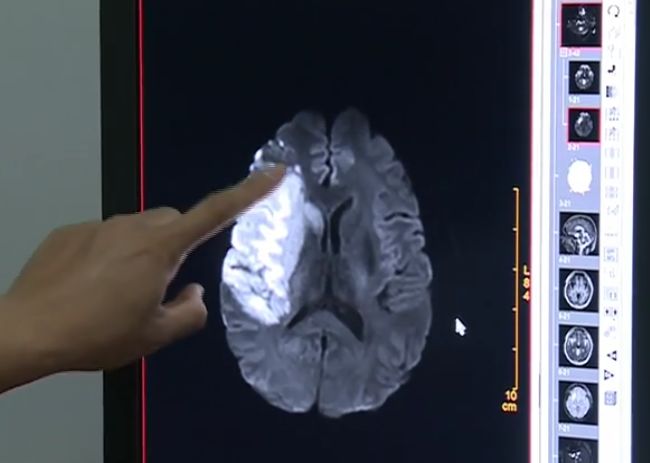

被发现瘫在床上无法动弹之后两个小时,吴先生被送到附近医院,一天后才转送到南方医科大学深圳医院神经内科。入院检查显示,他的大脑中动脉完全堵塞,右侧大脑大面积脑梗。

医生介绍,患者本身脑血管有点狭窄,现在右侧大脑大面积梗死。